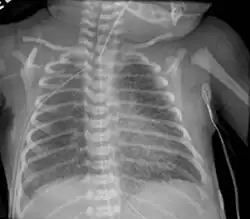

Infant respiratory distress syndrome most commonly occurs in less than six hours after birth in about 1% of all births in the United States.[9] The main risk factor is prematurity with the likelihood of it occurring going up to 71% in infants under 750g.[20] Other risk factors include infant of a diabetic mother (IDM), method of delivery, fetal asphyxia, genetics, prolonged rupture of membranes (PROM), maternal toxemia, chorioamnionitis, and male sex. The widely accepted pathophysiology of respiratory distress syndrome is it caused by insufficient surfactant production and immature lung and vascular development. The lack of surfactant makes the lungs atelectatic causing a ventilation to perfusion mismatch, lowered compliance, and increased air resistance. This causes hypoxia and respiratory acidosis which can lead to pulmonary hypertension. It has a ground glass appearance on an x-ray. Symptoms can include tachypnea, nasal flaring, paradoxical chest movement, grunting, and subcostal retractions.[9]

Meconium Aspiration Syndrome occurs in full term or post-term infants who aspirate meconium. Risk factors include a diabetic mother, fetal hypoxia, precipitous delivery, and maternal high blood pressure.[22] Its diagnosis is based on meconium stained amniotic fluid at delivery and staining on the skin, nails, and umbilical cord. Aspiration can cause airway obstruction, air-trapping, pneumonia, lung inflammation, and inactivated surfactant. It presents as patchy atelectasis and hyperinflation on an x-ray with a pneumothorax of pneumomediastinum also possible.[9]

Transient Tachypnea of the Newborn is caused by the retention of alveolar fluid in the lungs. It commonly occurs in infants who are delivered via caesarean section without the onset of labor because absorption of amniotic fluid in the lungs has not yet commenced. Other risk factors are male sex, macrosomia, multiple gestations, and maternal asthma. It usually presents with tachypnea and increased work of breathing. On an x-ray diffuse infiltrates, interlobar fissures, and sometimes pleural effusions can be seen. It is a diagnosis of exclusion because of its similarity to other diseases and frequently CPAP is used to help push the lung fluid into the pulmonary vasculature.[9][25]

Pulmonary interstitial emphysema is the condition of air escaping overdistended alveoli into the pulmonary interstitium. It is a rare disease that occurs most often in premature infants, even though it is possible to appear in adults.[26] It often presents as a slow deterioration with the need for increased ventilatory support. Chest x-ray is the standard for diagnosis where it is seen as linear or cystic translucencies extending to the edges of the lungs.[9]